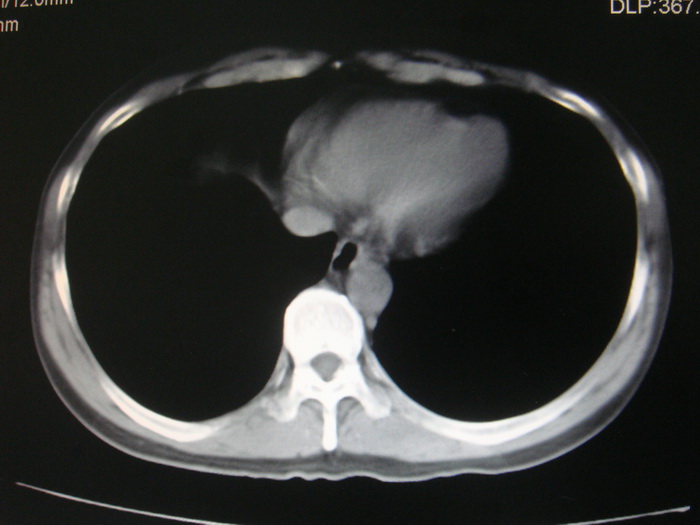

标题: CT28366:男性,45岁,偶尔发现右颈部肿块行胸部CT扫描。 [打印本页]

男性,45岁,偶尔发现右颈部肿块行胸部ct扫描。

两肺多发结节灶及纵膈淋巴结肿大考虑为转移

两肺多发性转移瘤,纵隔淋巴结转移。

两肺多发性转移瘤,纵隔淋巴结转移。食道中上段管壁似乎增厚,作相关检查。

两肺多发性转移瘤,前上纵隔淋巴结转移。